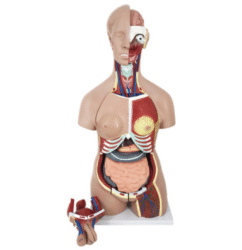

ATL-12 MALE MUSCLES FIGURE 2 PARTS

The model is an anatomically accurate representation of the human anatomy, complete with superficial and deep musculature, the digestive system, lymphatic system, respiratory system, urinary system, circulatory system, endocrine system, and nervous system. Our model has removable organs and dissectible features for a complete educational experience.

Classification:

Skeleton Models(human bone, muscle, etc.)